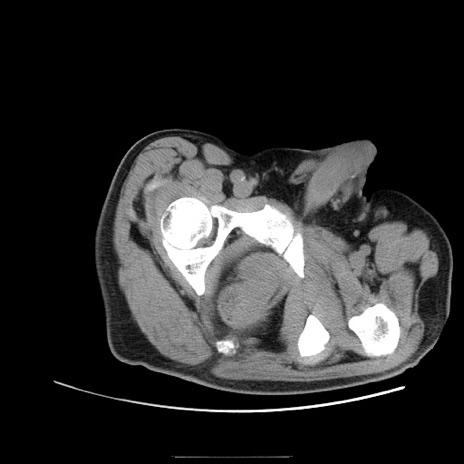

症例22(横断像)

【症例】50歳代男性

【主訴】腹痛

【現病歴】AVMからの被殻出血のため回復期リハ病棟入院中。 本日午後3時頃急に下腹部痛が出現した。

【既往歴】AVM、被殻出血、虫垂炎、高血圧

【身体所見】意識晴明、左半身不全麻痺、会話の理解は良好、36.5°C、腹部:膨隆、全体に板状硬、下腹部正中に圧痛点あり、反跳痛-、筋性防御不明、右下腹部にope scar

【データ】WBC 9400、CRP 0.06